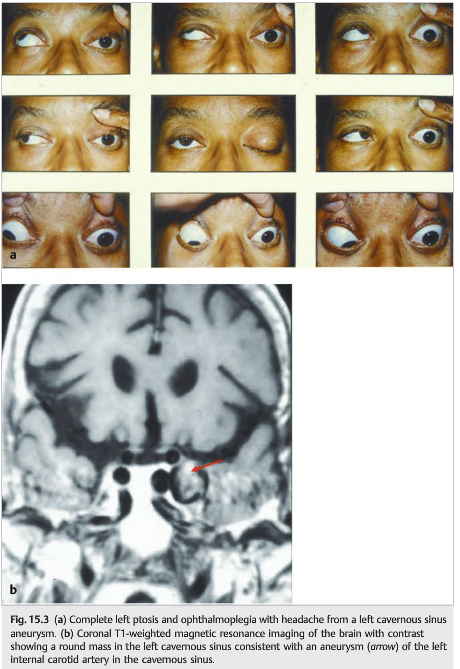

Aneurysms of the internal carotid artery may develop within the cavernous sinus (▶Fig. 15.3 and ▶Fig. 15.4).

They are often asymptomatic until patients develop diplopia (ocular motor nerve compression) and ipsilateral pain (trigeminal nerve compression).An ipsilateral third-order Horner syndrome may be present. There is usually no visual loss.